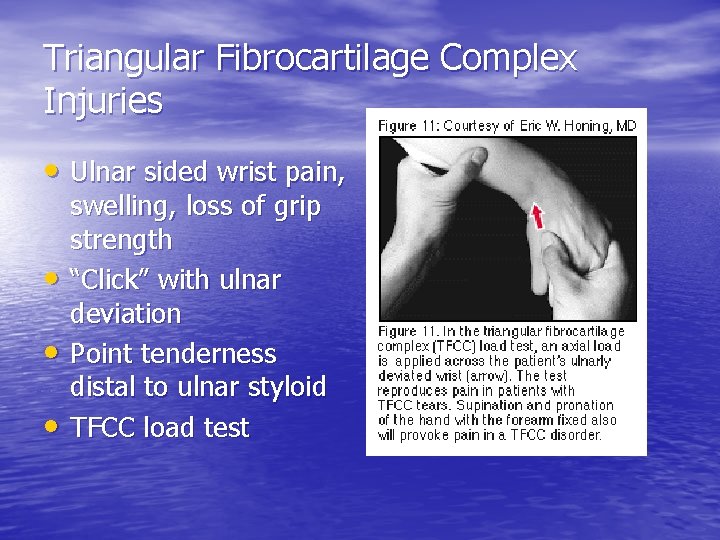

Triangular Fibrocartilage Complex Injuries • Ulnar sided wrist pain, • • • swelling, loss of grip strength “Click” with ulnar deviation Point tenderness distal to ulnar styloid TFCC load test